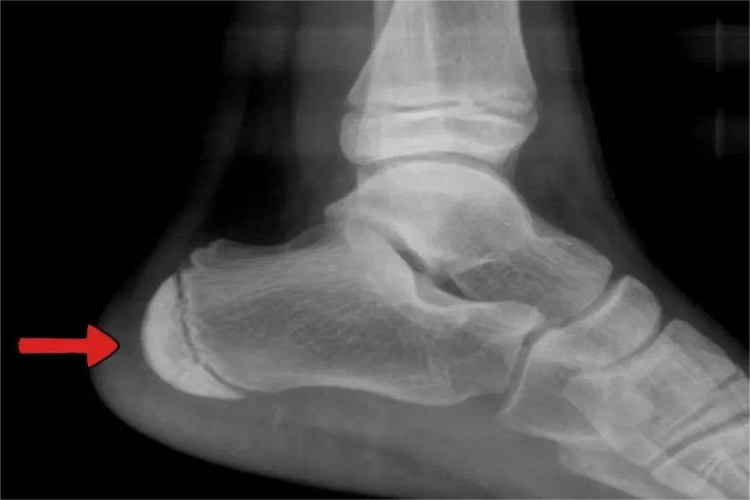

儿童跟骨骨骺出现异常时,可能为跟骨骨骺损伤或跟骨骨骺炎,X线表现如下:

跟骨骨骺损伤:跟骨骨骺损伤时,X线表现为跟骨骨骺出现移位,骺板增宽,临时钙化带变模糊或消失。

跟骨骨骺炎:跟骨骨骺出现炎症时,X线会见到跟底结节变扁平,密度呈不均匀增高,外形不规则,呈波浪状或虫蚀状,骨骺线增宽。